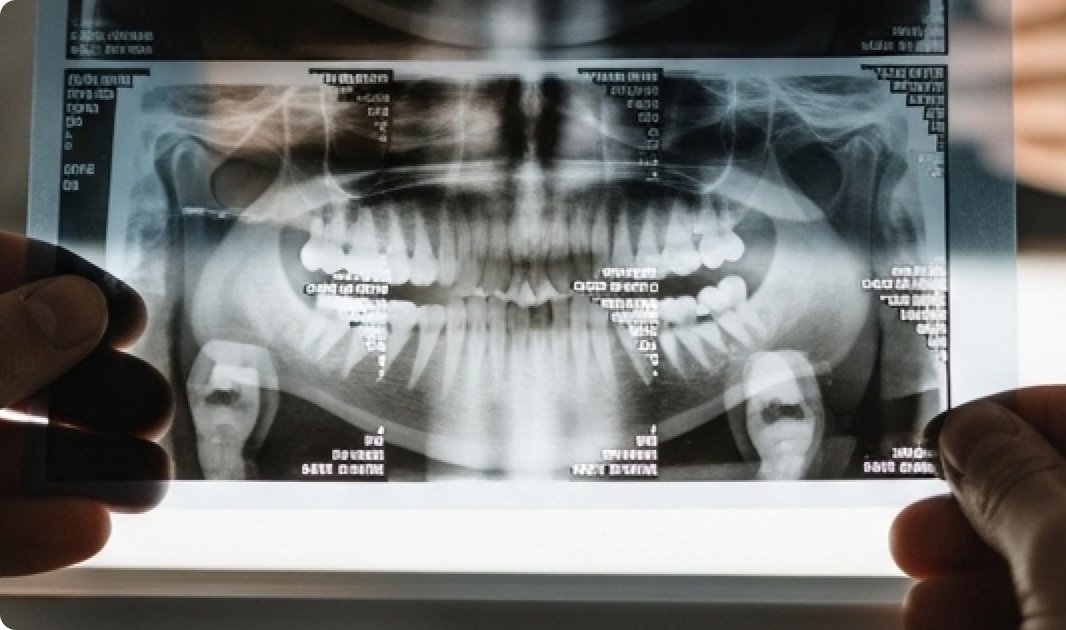

Mūsų klinikos išskirtinumas – nuosava dantų technikų laboratorija. Čia pat gaminami dantų protezai, laminatės ir kitos restauracijos, todėl pacientai gali džiaugtis greitesniu bei kokybiškesniu rezultatu. Glaudus odontologų ir technikų bendradarbiavimas leidžia pasiekti nepriekaištingą estetiką, tikslų pritaikymą ir ilgalaikį komfortą.